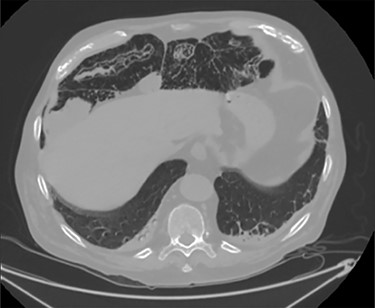

Unfortunately, once he returned home his temperature started to rise up to 38°C and he was readmitted to the hospital. A new contrast-enhanced Chest/Abdomen CT showed a bilateral pneumonia and a massive amount of intraperitoneal free gas, mainly in the abdominal upper quadrants (Fig. 2). No fat stranding, nondilated bowel, no vascular abnormalities and no free fluid were detected. Although the CT showed an evident worsening, the patient still remained completely asymptomatic on physical examination. Accordingly, he started to be treated with meropenem for pneumonia (Escherichia coli was isolated into the sputum) and he finally agreed to underwent diagnostic laparoscopy. Surprisingly, that was definitely not a case of pneumoperitoneum but an idiopathic PCI as we found multiple intramural air content cyst, about 2–3 cm in diameter, all around the small bowel loops and mesentery (Fig. 3). No intra-abdominal maneuvers were made. The patient had an unremarkable recovery (Clavien–Dindo classification grade was 1) [3] and he was discharged home on postoperative Day 15 in well condition, once he had recovered from pneumonia.

A moderate amount of intraperitoneal gas is present anteriorly to the small bowel.